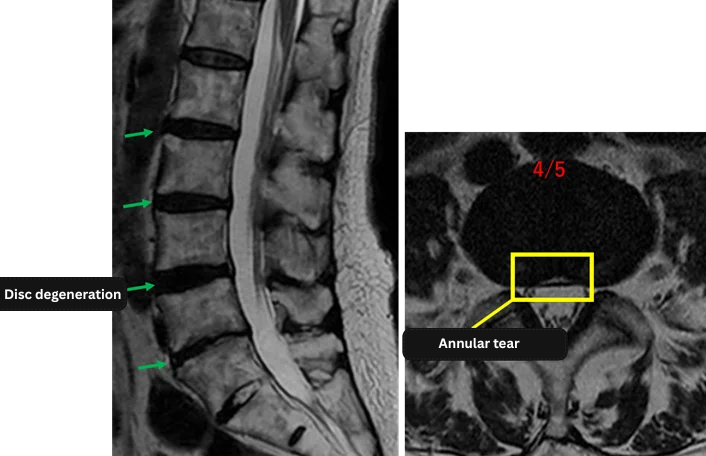

Imaging and findings

L1/2: No abnormal findings

L2/3: Mild disc degeneration

L3/4: Disc degeneration

L4/5: Disc degeneration, disc bulging, annular tear

L5/S: Disc degeneration, disc bulging

The above findings were also observed on the imaging.

Disc degeneration, disc bulging, and annular tears were observed at L2/3, L3/4, L4/5, and L5/S, which are considered highly likely to be the cause of the patient’s main symptoms.

This is an image of the Discogel inserted into the intervertebral disc.